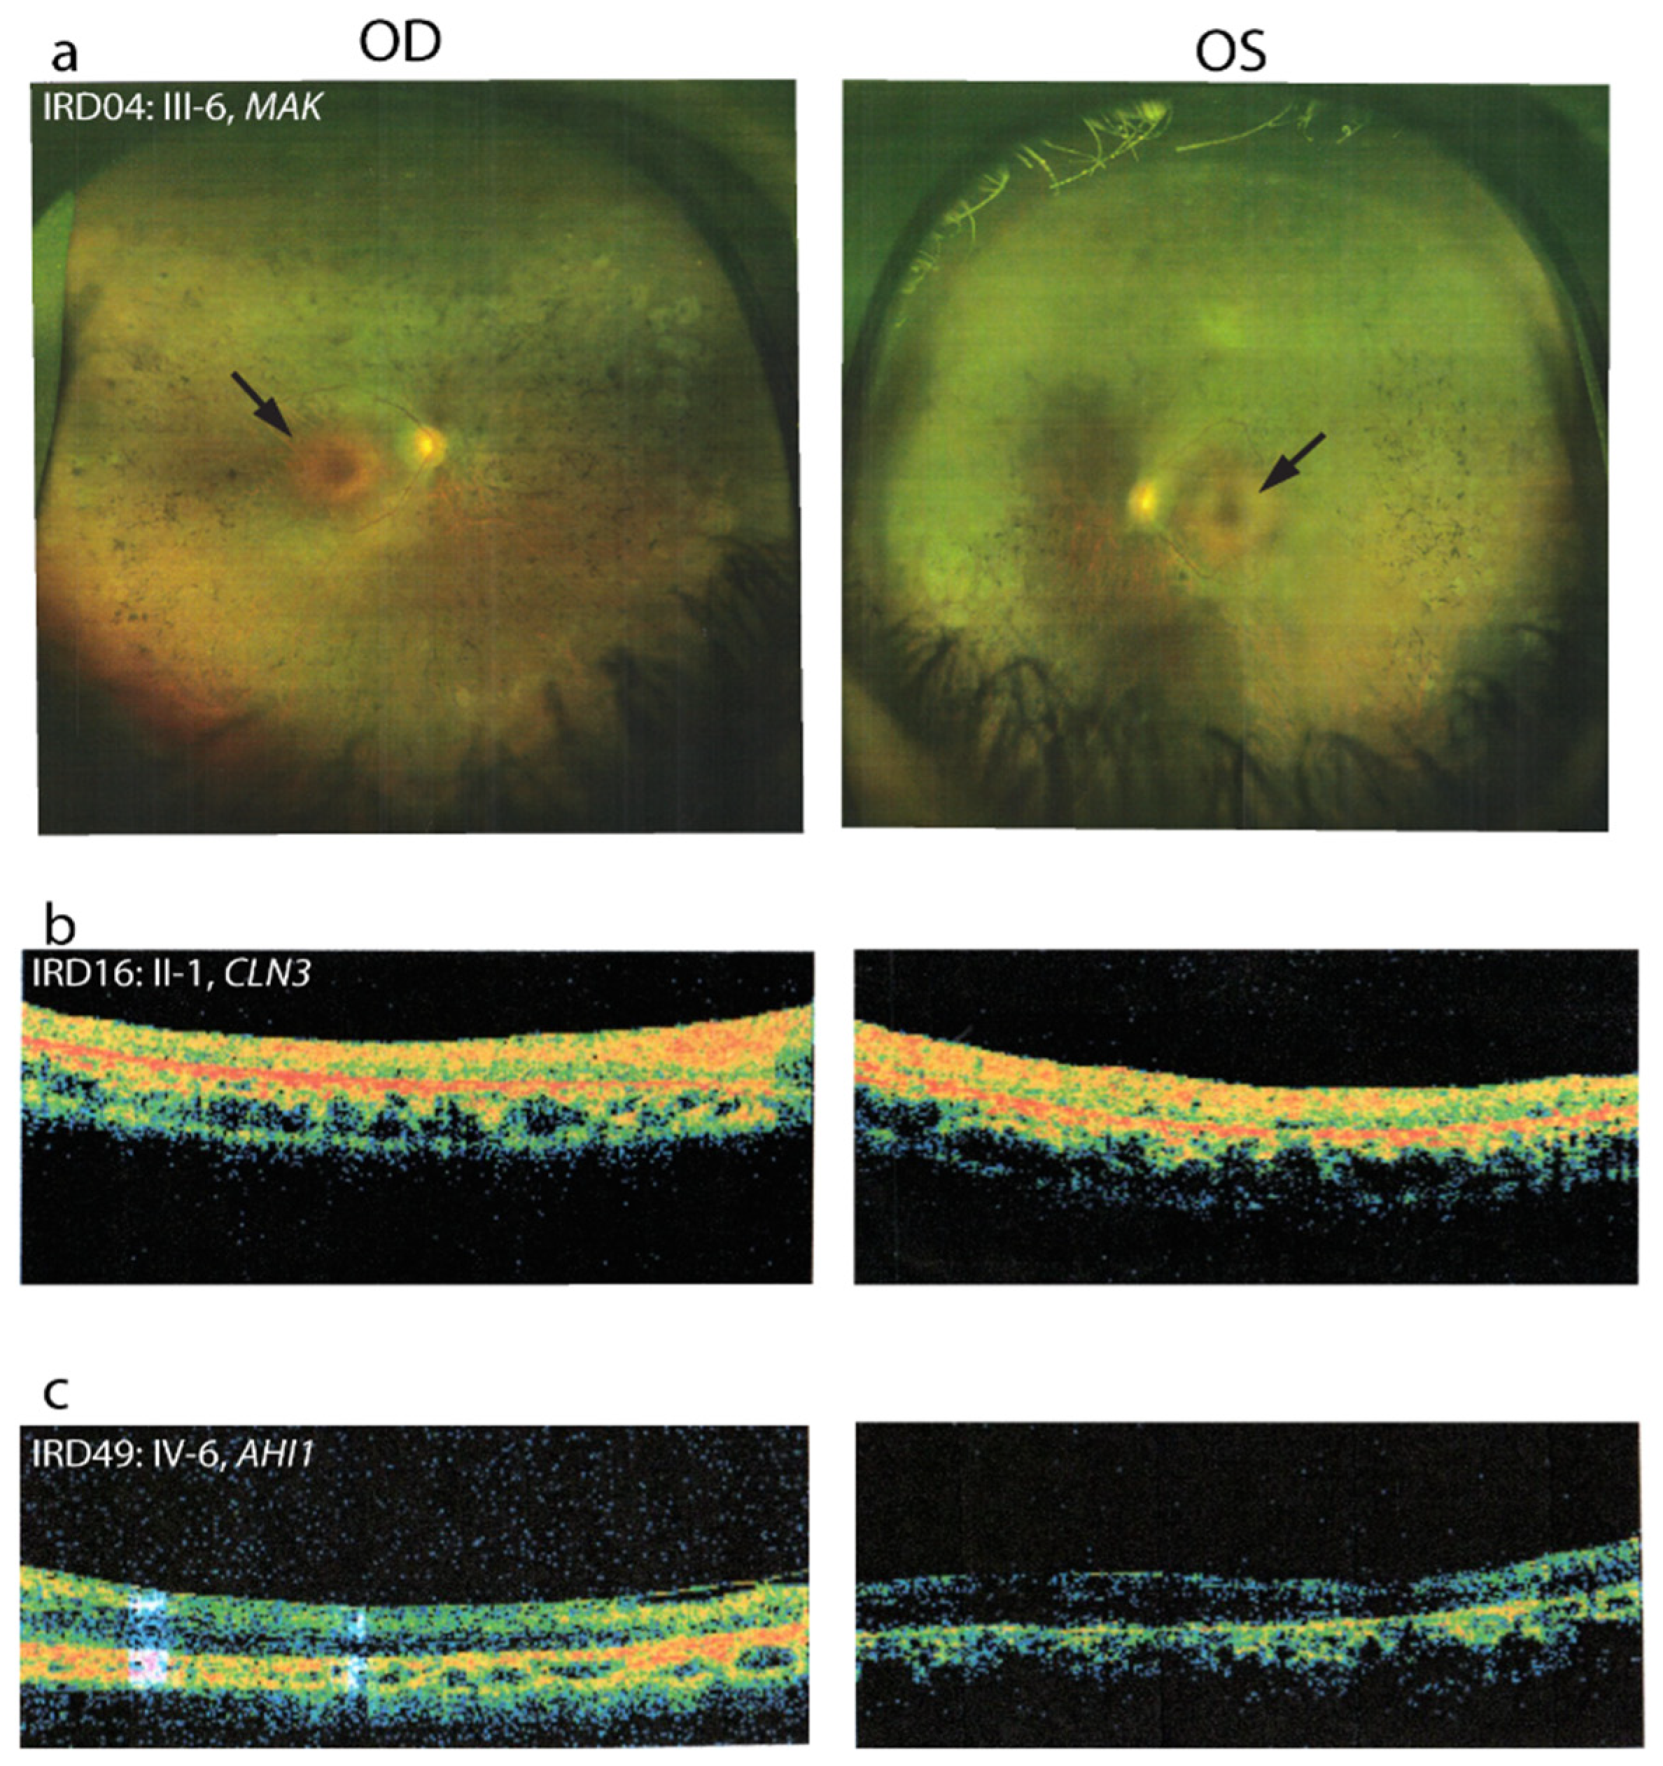

| IRD04 | MAK | Chr6:10804098 | NM_001242957.1: c.518G > T; p.(Arg173Ile) | NA | NA | NA | Hom | Yes | D, D, DC | VUS | Novel | ||

| IRD16 | CLN3 | Chr16:28493482 | NM_001042432.1: c.1000C > T; p.(Arg334Cys) | rs386833694 | NA | NA | NA | Hom | Not done | LP | D, D, DC | VUS | [56,57] |

| IRD49 | AHI1 | Chr6:135752384 | NM_017651.4:c.2335G > A; p.(Asp779Asn) | 3.2 × 10−3 | NA | 3.2 × 10−3 | Hom | Yes | VUS | T, D, N | VUS | ClinVar | |